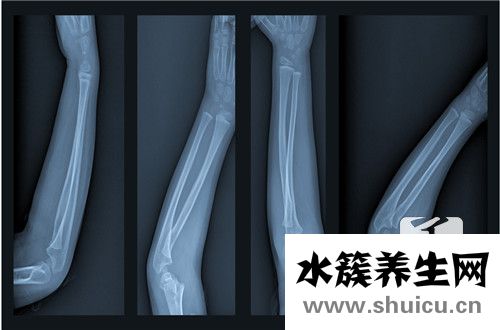

無論人體出現在哪個位置骨折,都不可能行走。對于小腳趾 骨折,也不可能走可以。所以對于經常走路的盆友來說,要多注意休息,腳要足。在小腳趾骨折,要注意雙腳的保養,掌握小腳趾骨折,才能達到可以立即就醫...